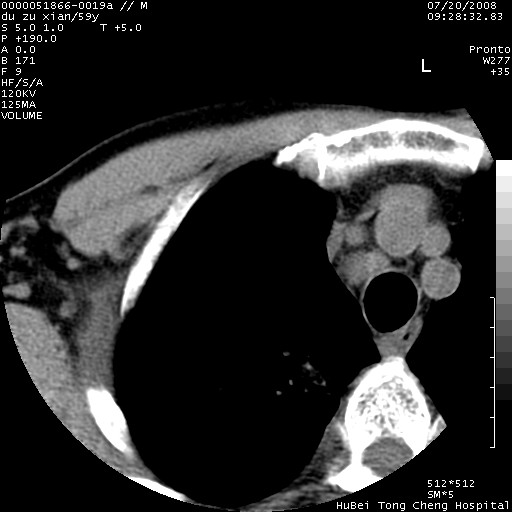

以下是引用宇宙ct在2008-8-25 23:21:00的发言:[br]右肺周围性肺癌并肋骨转移,纵隔淋巴结转移。

以下是引用zsl6918在2008-8-25 22:40:00的发言:[br]右肺周围性肺癌并肋骨转移,纵隔淋巴结转移。

以下是引用zy_zj在2008-8-26 15:24:00的发言:[br]单从病变本身,我倾向良性炎性病变,但肋骨转移了,所以说是考虑右肺周围性肺癌并肋骨、纵隔淋巴结转移可能性大。